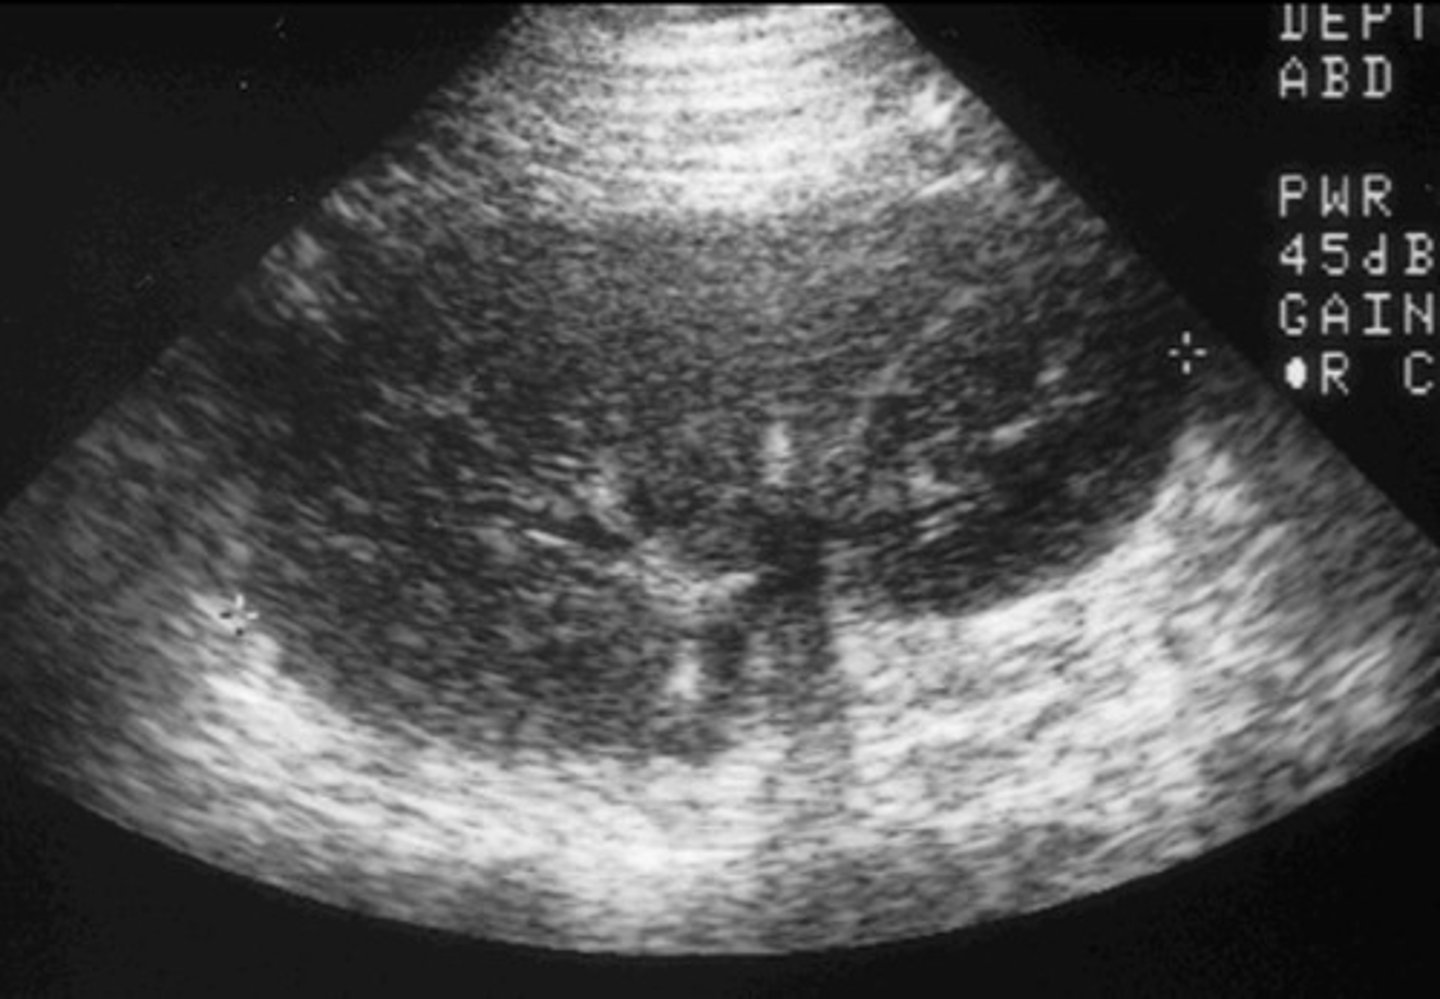

Appearance of Chronic Transplant Rejection

Echogenic kidney

Loss of corticomedullary boarders

Solid material in renal pelvis